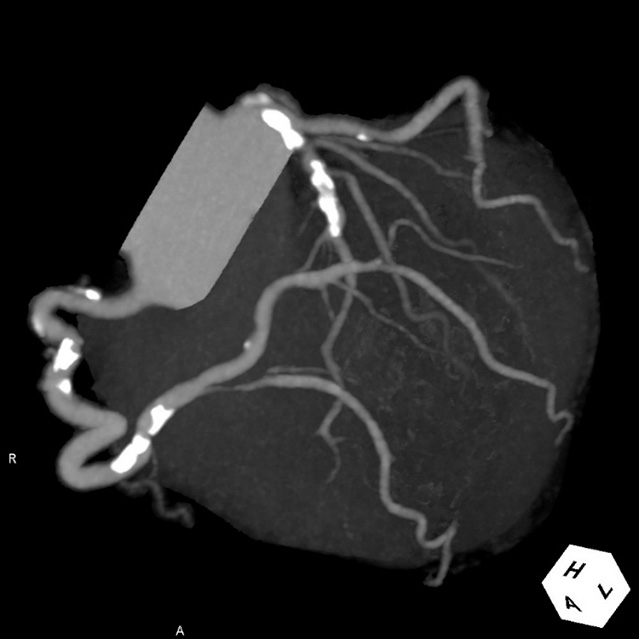

画像診断装置・放射線治療装置紹介

X線CT装置

64列 MDCT Aquilion CX (canon)

80列 MDCT Aquilion PRIME (canon)

80列 MDCT Aquilion PRIME SP(canon)

大きなトンネルの中に体を入れて、X線をあてて体の輪切りの写真を撮ります。CT検査には、単純CT検査と、造影剤を注射して撮影する造影CT検査があります。